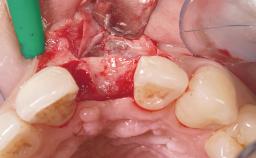

Late Flapless Placement of an Implant in a Maxillary Left Central Incisor Site

A 39-year-old male patient presented with a chief complaint of discomfort and gingival discoloration around his maxillary left central incisor. He was in good general health and was a non-smoker. His past dental history was significant because of the traumatic fracture of tooth 21 in a sporting accident at age 13. Initial dental treatment included endodontic therapy and a full-coverage restoration. The patient became symptomatic 5 years later, when structural failure of the tooth resulted in the dislodgment of the crown. Endodontic retreatment, apical surgery, and post-and-core restoration were performed.

Bone Augmentation Horizontal|Staged

Augmentation Materials Xenogenous|Membrane

Soft Tissue Grafting Simultaneous

Bone Volume Deficient horizontally, requiring prior grafting